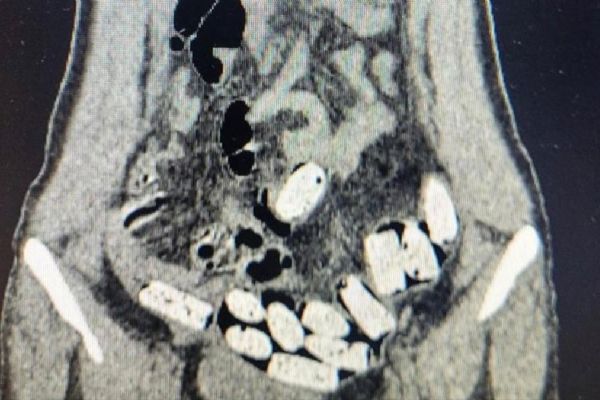

Bağırsakta uyuşturucu ticareti! 3 İranlı kadın tutuklandı

Rize'de iç çamaşırı ve bağırsaklarına gizledikleri 868 gram sentetik uyuşturucuyla yakalanan İran uyruklu 3 kadın tutuklandı. Beden muayenesi için hastaneye götürülen şüphelilerin bağırsaklarında da 868 gram uyuşturucu bulundu.

Zanlıların iç çamaşırlarına saklanmış 9 kapsül şeklinde sentetik uyuşturucu ele geçirildi. Beden muayenesi için hastaneye götürülen şüphelilerin bağırsaklarında da 868 gram uyuşturucu bulundu.